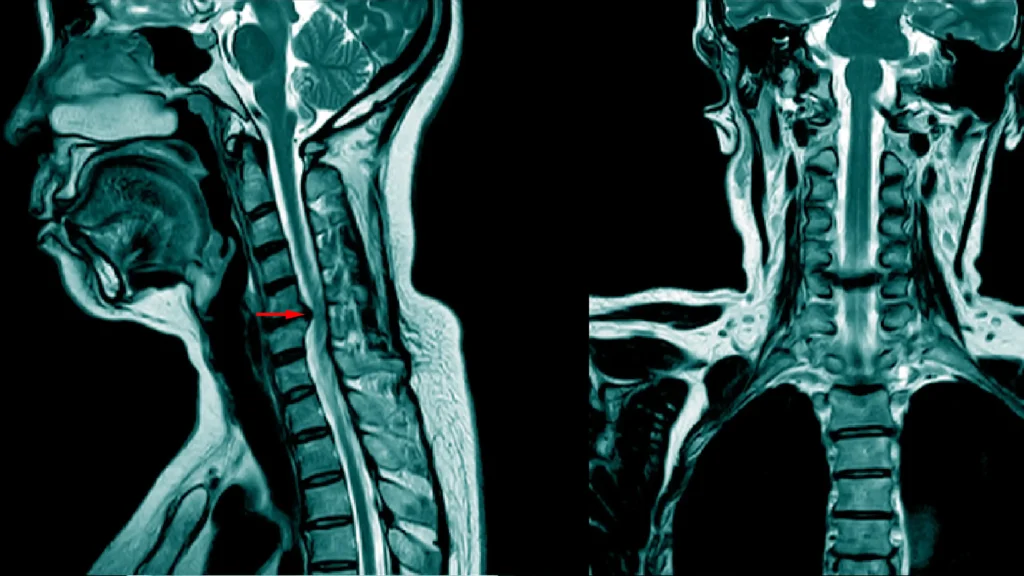

If you suffer from the pain or discomfort of a pinched nerve on a fairly regular basis — and especially the same one — it is time to see a doctor. Problems such as herniated discs can lead to chronic (sometimes intermittent) flare-ups that will likely worsen over time.

If all else fails, there are several excellent surgical options available for impingements. These should always be performed by a well-seasoned neurosurgeon with a specialization in the procedure you are having performed. Neurosurgery has come light years from what it once was — whereas a discectomy 20 years ago may have landed you in the hospital for weeks and then unable to do much for months, new techniques now allow for very short recoveries and little-to-no expectation for follow-up procedures. Surgeries commonly performed for pinched nerves include posterior cervical foraminotomy and microdiscectomy, anterior disc surgery and minimally invasive lumbar fusion, just to name a few.